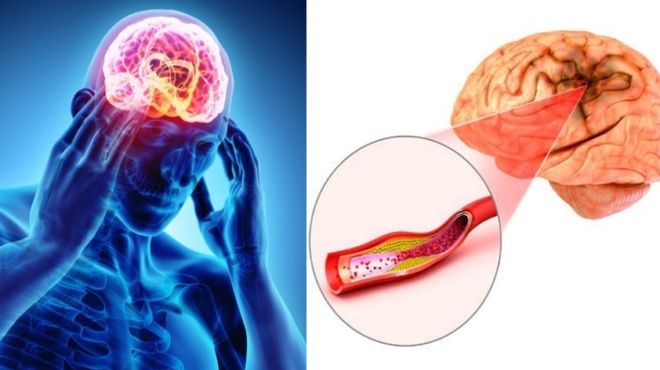

Η σύγχυση, οι δυσκολίες στην άρθρωση και η μυϊκή αδυναμία είναι τρία κοινά συμπτώματα που εκδηλώνονται. Η ξαφνική εμφάνιση τους ομως μπορεί να υποδηλώνει πιθανό εγκεφαλικό επεισόδιο.